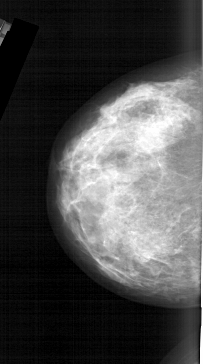

A_1566_1.LEFT_MLO

LEFT_MLO LINES 6346 PIXELS_PER_LINE 3751 BITS_PER_PIXEL 12 RESOLUTION 43.5 NON_OVERLAY